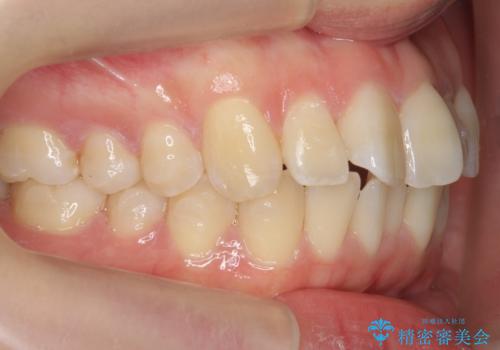

インビザライン モニター治療 前歯のねじれをまっすぐに

- 前歯のねじれを主訴に来院。

インビザラインの部分矯正コースではなく全体矯正コースをご希望でした。

前歯のねじれやがたつきだったため、モニター治療での低価格でのご提案が可能でした。

年齢が10代なこともあり、歯の動きは非常によく、リファインメントなしできれいに並びました。

下の前歯を少し削合して並べています。